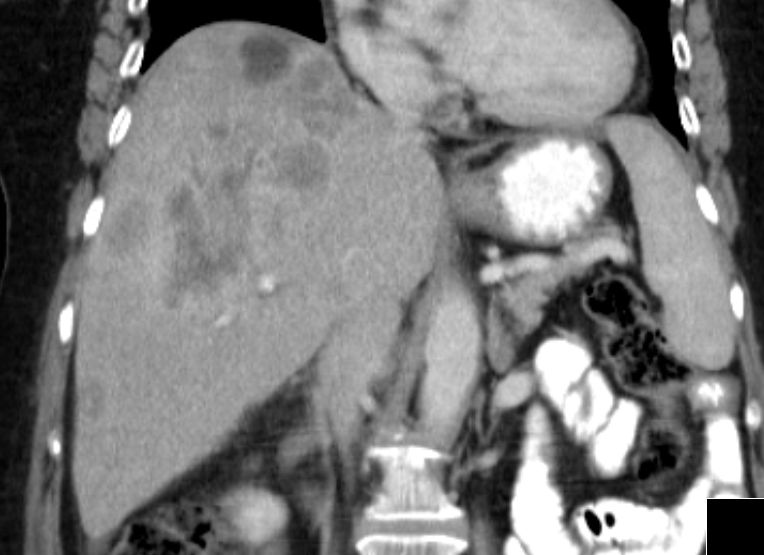

primär hepatisch metastasiertes Sigmakarzinom![]() |